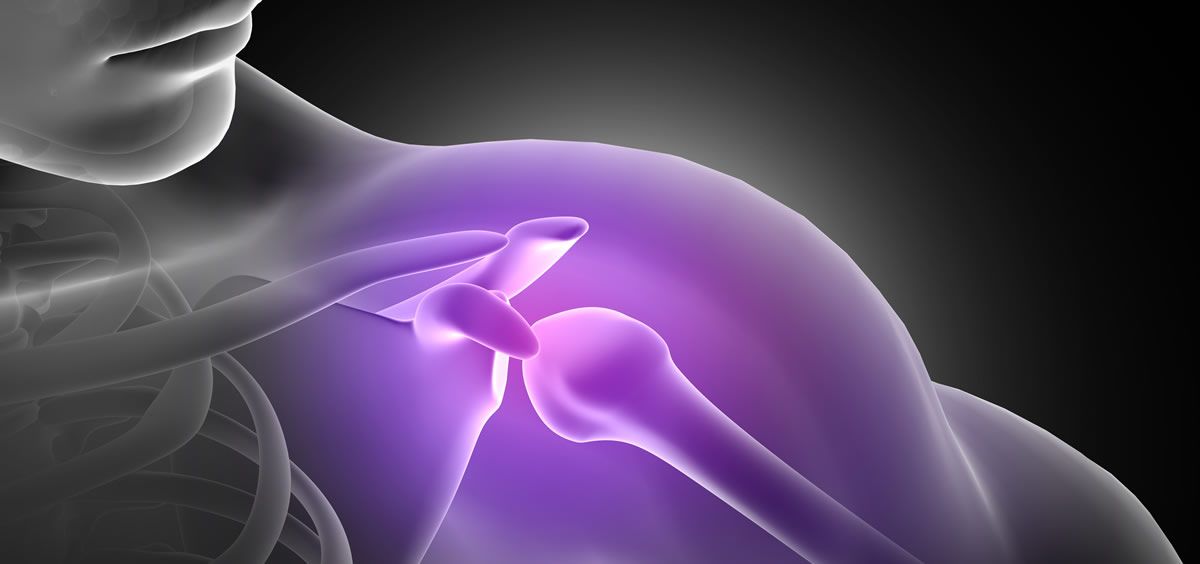

Un grupo de investigadores de la University of Science and Technology (Corea del Sur) y la Facultad de Medicina de Harvard, ha desarrollado una plataforma de tejidos complejos para restaurar los manguitos rotadores dañados. La bionita de matriz extracelurar para el tejido se utiliza para la bioimpresión en 3D, con el objetivo de imitar con precisión la estructura de los manguitos rotadores.

El sedentarismo es cada vez más habitual en la sociedad, un sector de los jóvenes desarrolla dolores propios de edades más avanzadas, como es el caso de las molestias en los hombros. Un ejemplo de ello son los oficinistas que pasan horas y horas sentados frente a un ordenador, viéndose afectados de múltiples dolores de músculos y huesos.

Los expertos señalan que la regeneración del manguito rotador supone un gran reto. El equipo desarrollador de la plataforma, experimentó sus efectos en ratas con desgarros de espesor total del manguito rotador y observó la regeneración de sus tejidos y la recuperación de la función del hombro. Los resultados confirmaron que esta plataforma puede regenerar los manguitos rotadores a través de las células madre.